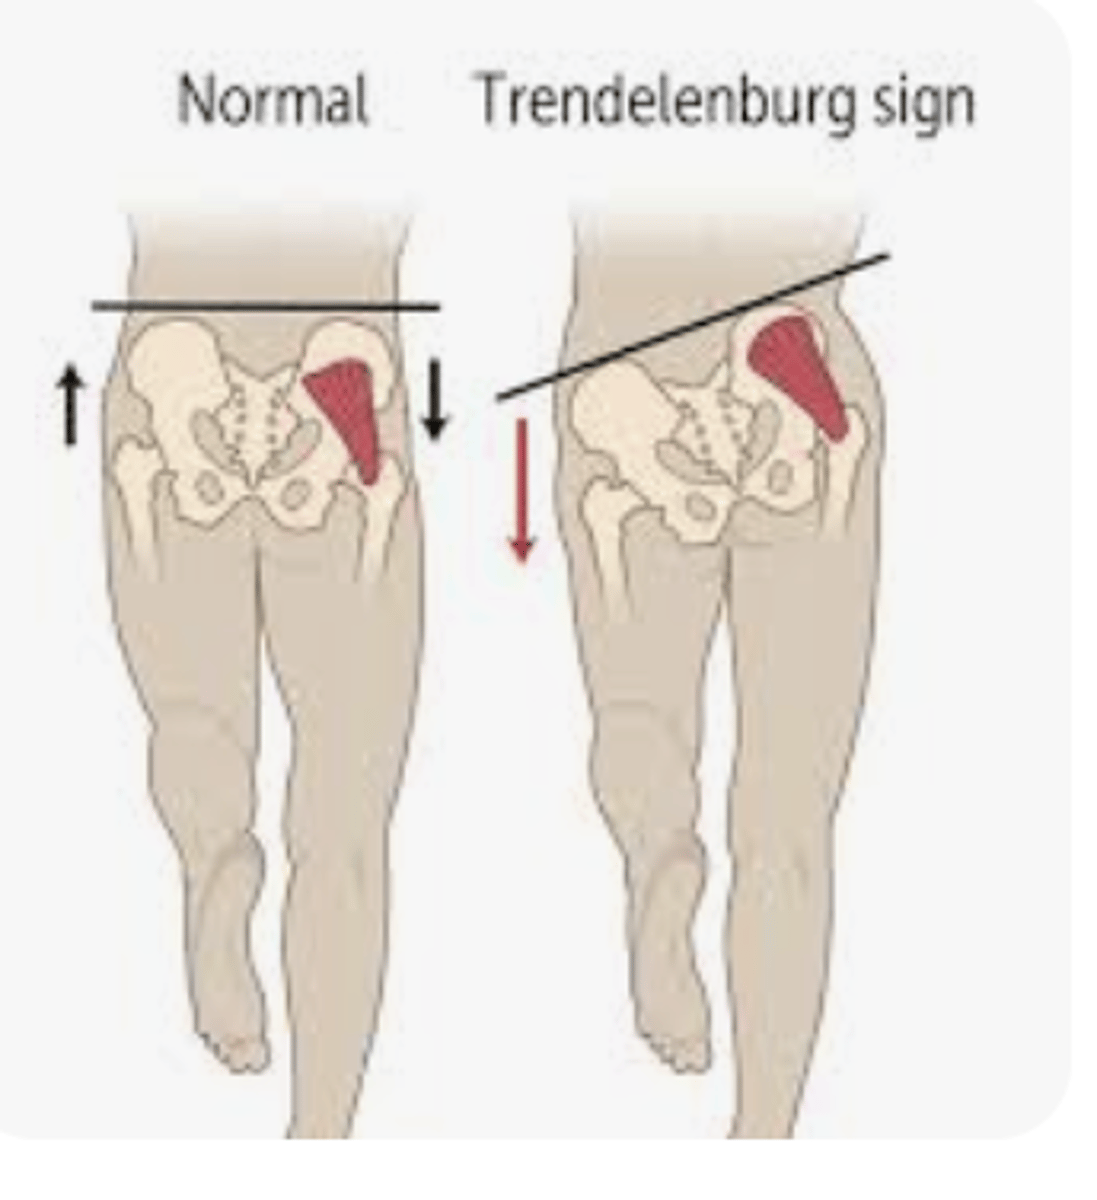

Trendeleburg Sign

Gluteus medius endurance weakness

C/L hip drop